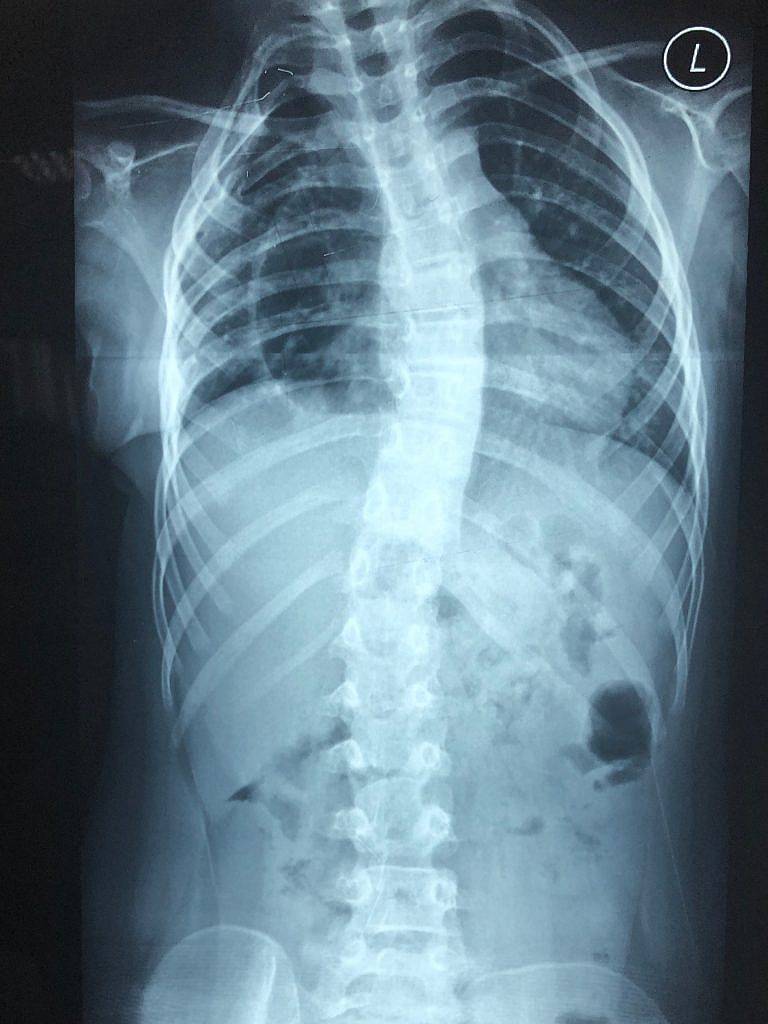

• Hip anteriorly rotates causing a spinal imbalance, leading to scoliosis in growing children

• Scoliosis

Diagnosis of malalignment syndrome is derived clinically after a thorough history of symptoms that is accompanied by a clinical examination and kinetic/gait assessment. If joint damage is suspected, x-rays may be requested to determine the extent of damage accumulated specifically in the knee, ankle, mid-foot or big toe joints.